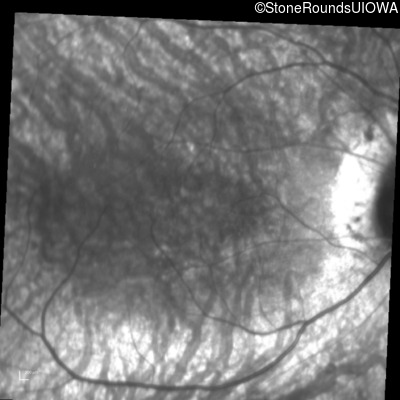

Infrared Fundus Photograph - Left - 20/100 sc

Exemplar